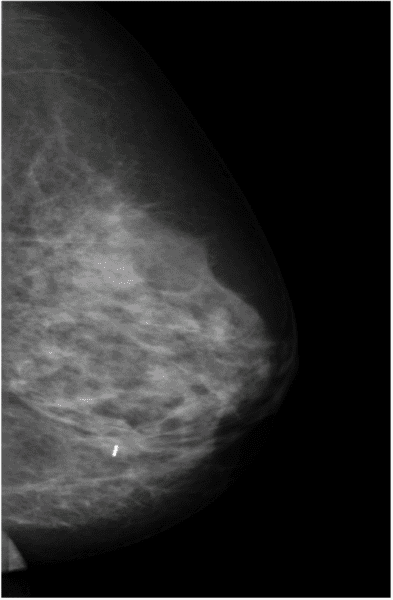

Het zaadje is vier millimeter groot. Het geeft een hele lage dosis straling af, die niet schadelijk is voor uw gezondheid of die van uw omgeving. Tijdens de operatie wordt de straling van de markering met een detector gemeten. Op deze manier kan de afwijking in de borst of lymfeklier opgespoord worden. Daarna wordt de afwijking met het zaadje uit uw borst of lymfeklier verwijderd. De operatie kan kort na de plaatsing van het zaadje uitgevoerd worden, maar er kunnen ook weken tot maanden tussen zitten. Onderstaande foto’s zijn een voorbeeld van een borst waarin de tumor is gelokaliseerd met een radioactief zaadje.

Een röntgenopname van een borst waarin de tumor is gelokaliseerd met een radioactief zaadje.